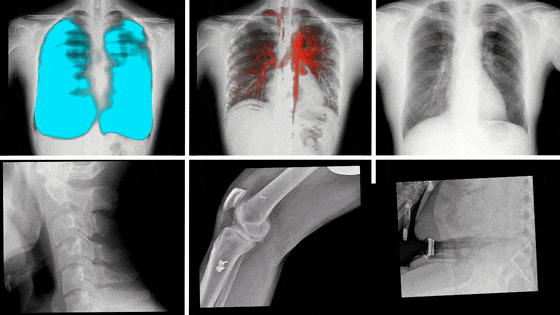

动态DR影像

动态DR,是近些年来迅速发展的影像技术,其具备动态/静态两种模式,这意味着除了能像传统静态DR进行普通的X片拍摄外,还能通过高帧率、多角度的采集技术,捕捉拍摄部位的实时动态,将短时间内拍摄的数百张图像合成为一个动态视频。